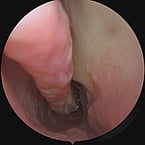

Deviated Nasal Septum

Deviated Nasal Septum is a significant shift in the nasal septum which can obstruct sinus drainage and airflow, contributing to sinus infections and congestion and sometimes nosebleeds, and snoring . A surgical procedure called septoplasty is done to correct this issue. A hole or opening in the nasal septum is called a Septal Perforation a condition that may result from various causes such as trauma, certain medications, underlying medical conditions or cocaine use. Even though conservative treatments can help manage this problem, surgical correction offers a permanent resolution.